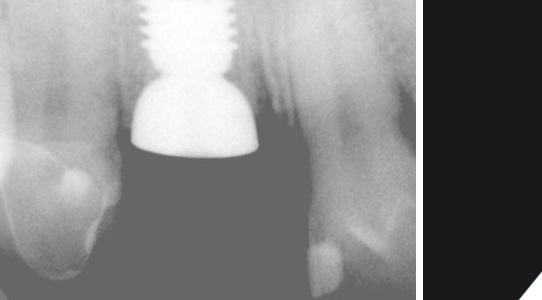

Die Kontrolle durch Röntgenaufnahmen.

Der Zahnarzt kontrolliert, ob die Einheilphase gut verläuft.